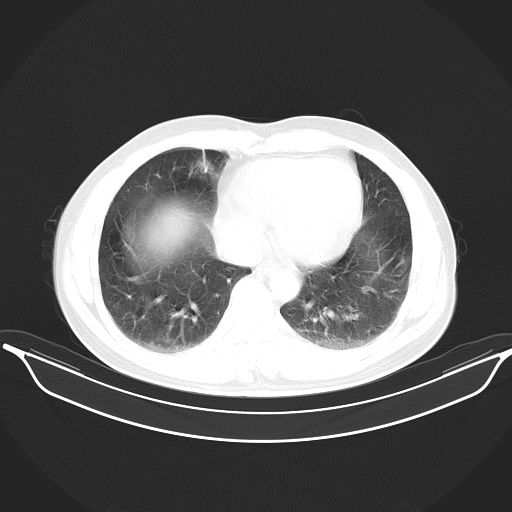

标题: CT25490:男,40岁,体检发现;无其它不适。 [打印本页]

标题: CT25490:男,40岁,体检发现;无其它不适。

考虑右下肺周围性肺癌并肺内多发转移,纵隔淋巴结转移!

支持 !考虑右下肺周围性肺癌并肺内多发转移,纵隔淋巴结转移,(气管前腔静脉后,隆突下,主动脉弓下都有了)

1、均为转移,原发灶不在肺内。2、肺癌肺转移。

考虑肺癌并肺内转移可能性大。

转移性肺肿瘤不排除,建议结合相关检查考虑